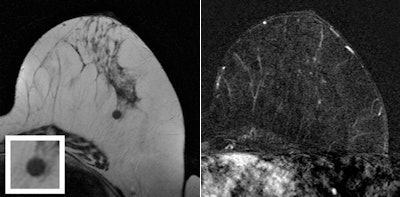

Of the 353 lesions, 66 (18.7%) were true-positive (23 cases of ductal carcinoma in situ and 43 invasive cancers) and 287 (81.3%) were false-positive. MR showed no breast cancer in 92% of the false-positive findings (264 of 287) and helped confirm the presence of breast cancer in 63 of 66 malignancies, according to the authors.

Breast MR identified all mammographic findings of invasive cancer and 18 of 21 mammographic findings that showed ductal carcinoma in situ (DCIS). It identified all 18 ultrasound findings that were invasive breast cancer and two that were pure DCIS, Strobel and colleagues found.

MRI had a relatively high false-negative rate for DCIS found on mammography, at 12%; the three false-negative cases were low-grade, at 6 mm, 7 mm, and 11 mm. On the other hand, breast MR found additional invasive cancers in three women with false-positive findings from mammography and ultrasound.

As for mammographic findings other than microcalcifications, MRI increased the positive predictive value (PPV) from 17.5% to 78%, with a false-negative rate of zero. For all ultrasound findings, MRI increased PPV from 12.9% to 69%, again with a false-negative rate of zero. MRI resulted in false-positive findings that led to MRI-guided biopsy in five of the 340 patients (1.5%).